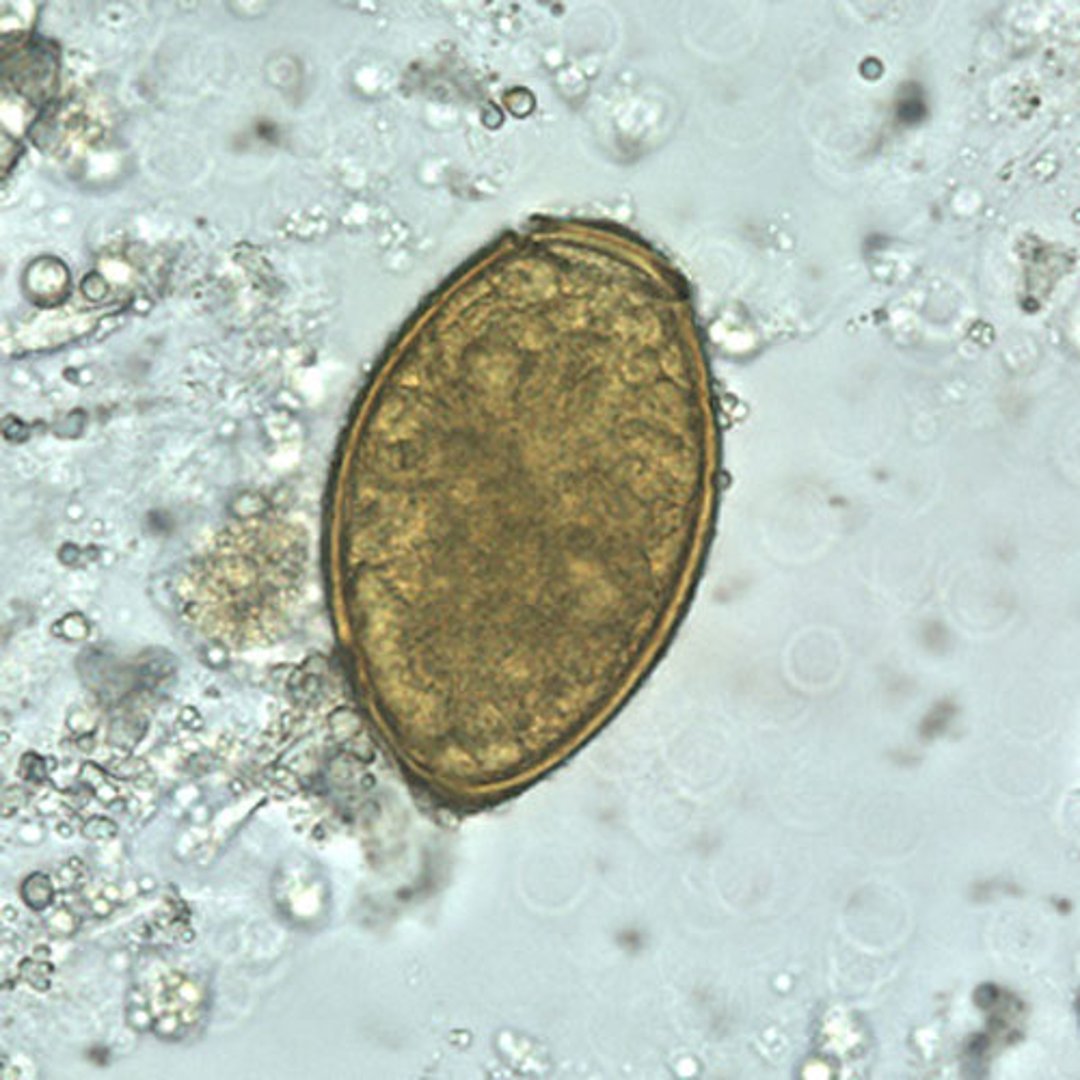

P. westermani eggs range from 80 to 120 micrometers long by 45 to 70 micrometers wide. They are yellow-brown, ovoid or elongate, and have a thick shell. The eggs are often asymmetrical with one end slightly flattened. At the large end, the operculum is clearly visible. The abopercular end is thickened.

The eggs are unembryonated when passed in sputum or feces.

CDC/DPDx